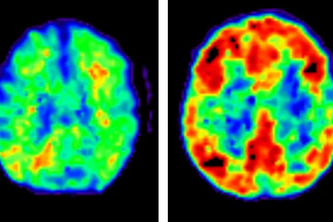

Challenge 3: Detecting Alzheimer's disease from EEG, a step to early detection to Alzheimer's!